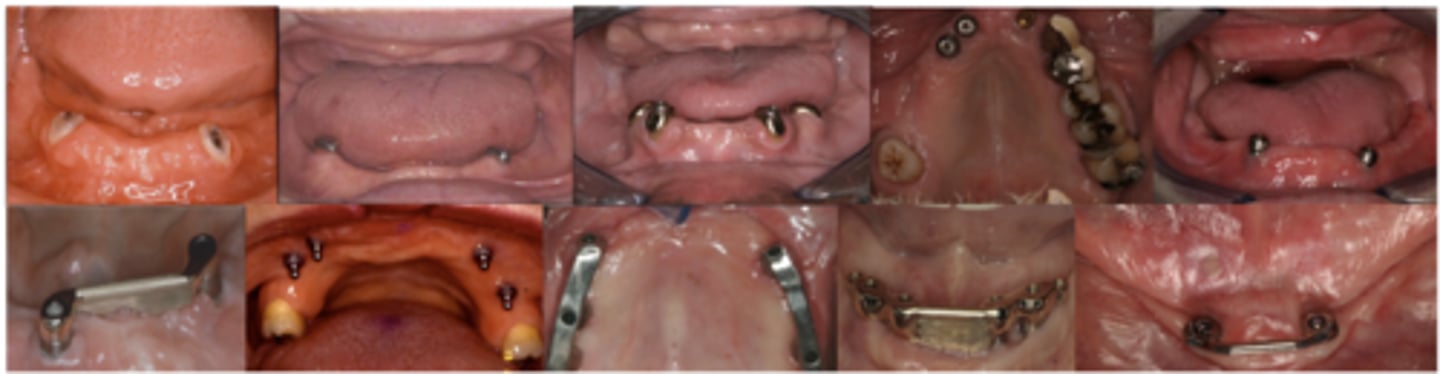

Types of overdentures

What do the following show?

Mucosal inserts

What are these images showing?

Implant-assisted removable complete denture